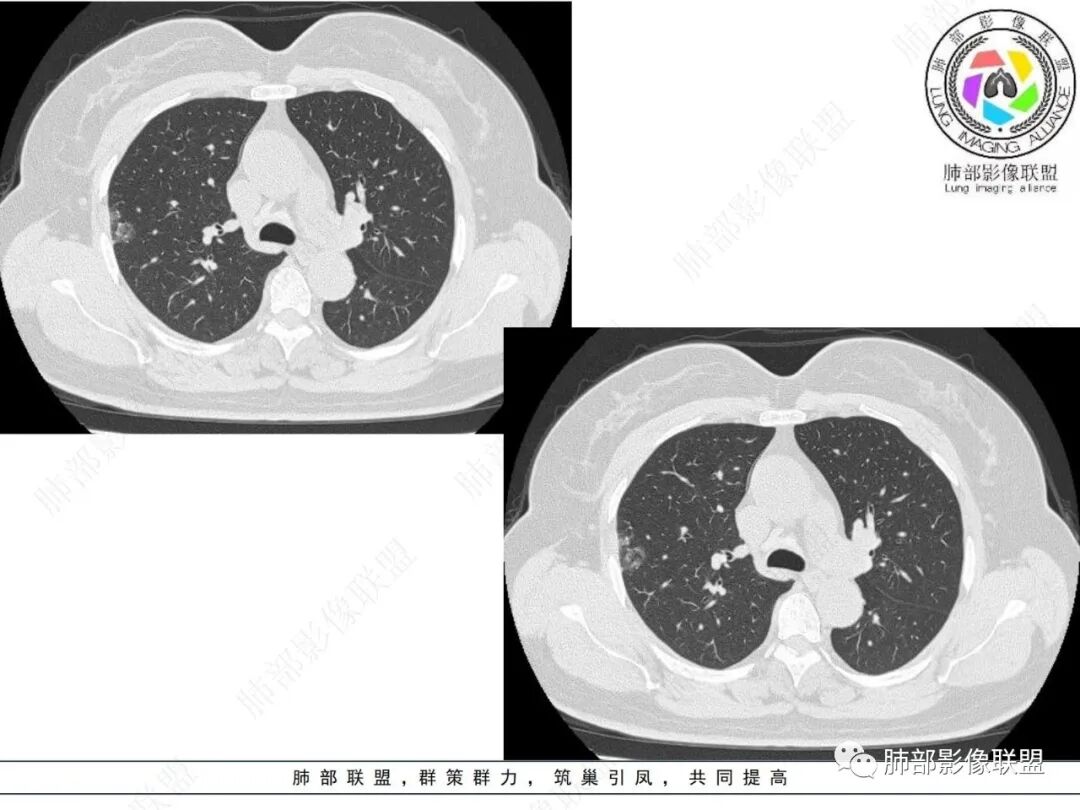

1.临床特点:57岁女性,体检发现阴影。

2.影像特点:

右肺上叶胸膜下混合磨玻璃团片影。

周围磨玻璃部分间杂条索状高密度区,密度欠均匀(可疑重力分布趋势),其磨玻璃影边界大多较清楚或可分辨,部分“L型”边缘,提示小叶间隔阻挡可能。血管穿行自如,可疑远端支气管进入。

实性部分较密实,不规则,隐约见棘突或刺状突起,未见钙化、空洞或液化区,实性边缘可见斑状略低密度间隙(借用王兆宇老师课件,称其呈“松软”的形态)。动脉期实性部分较明显不均匀强化,如果有完整增强图,还可以观察内部血管情况。

纵隔窗相对肺窗病灶相对小,仅部分实性影呈现。病灶张力不高,相邻胸膜增厚(糊墙),未见明显胸膜牵拉凹陷。

未见卫星病灶,远处未见磨玻璃结节影。

双肺门及纵隔未见明显增大淋巴结。心包及胸腔未见积液。